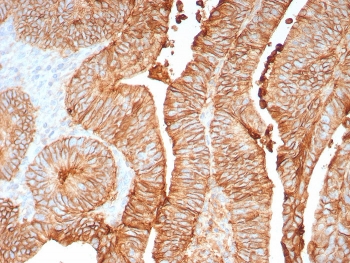

Immunohistochemistry of CDH17 antibody in human colon tissue. The recombinant rabbit mAb clone CDH17/8158R demonstrates strong membranous HRP-DAB brown staining along the lateral borders of colonic epithelial cells, consistent with Cadherin 17 localization in intestinal epithelium. Staining highlights well-organized glandular crypt structures with preserved epithelial polarity, while surrounding stromal tissue shows minimal background signal. The negative control inset, using PBS in place of the primary antibody, shows no specific staining. Heat-induced epitope retrieval was performed by boiling tissue sections in pH 9 10mM Tris with 1mM EDTA for 20 minutes followed by cooling prior to incubation.

Aberrant CDH17 expression has been reported in colorectal adenocarcinoma, gastric carcinoma, pancreatic adenocarcinoma, and other gastrointestinal malignancies. In tumor tissues, Cadherin 17 typically demonstrates strong membranous staining in well-differentiated epithelial tumor cells, reflecting preservation of intestinal lineage characteristics. Altered or reduced expression patterns may correlate with tumor progression or dedifferentiation in certain contexts. CDH17 antibody is therefore frequently applied in studies of gastrointestinal tumor biology and epithelial lineage analysis.